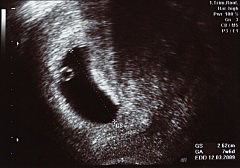

Periodo germinal 2

La blástula recién formada entra al útero donde flota por otros tres o cuatro días, antes de que su capa interna, llamada blastocisto, empiece a adherirse al recubrimiento interno del útero (el endometrio) en un proceso llamado implantación.

Periodo germinal 3

El blastocisto implantado libera una enzima que literalmente abre un hueco en el tejido suave y esponjoso del endometrio hasta enterrarse por completo en la pared uterina. Aproximadamente 10 días después de que la blástula entra al útero, la implantación del blastocisto se ha completado.